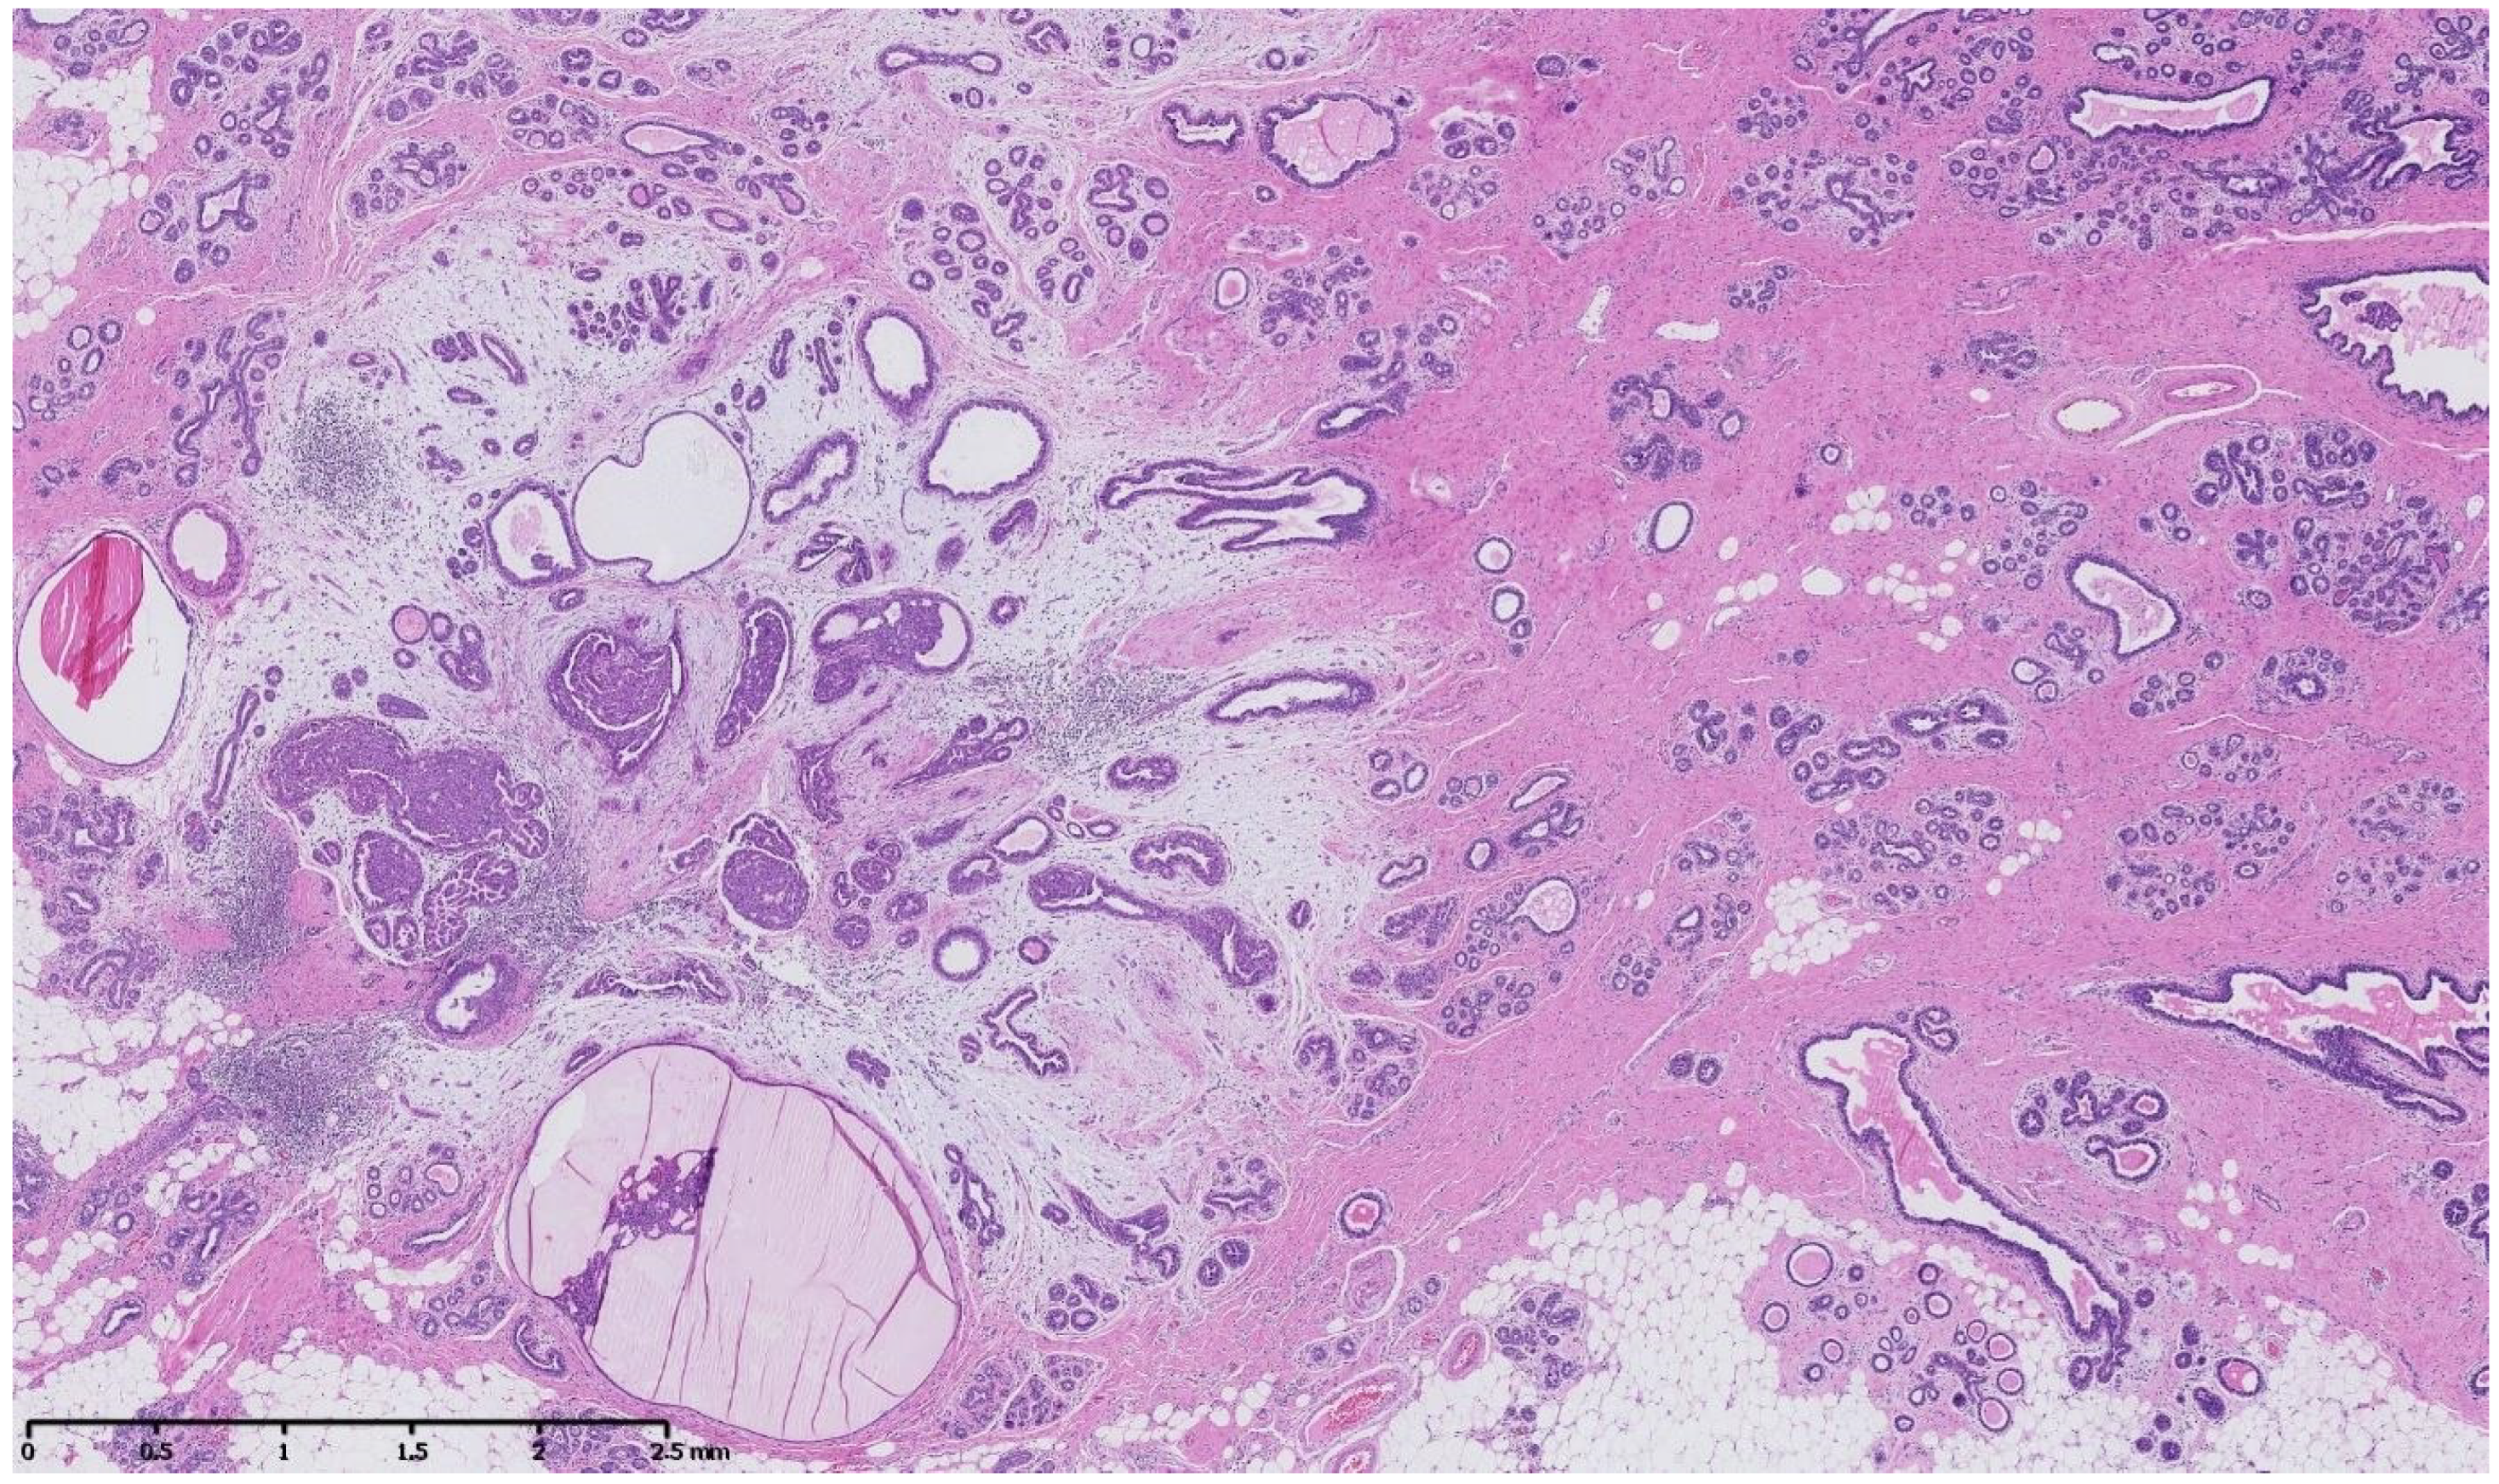

4. Benign Breast Lesions in Transwomen

1. Introduction